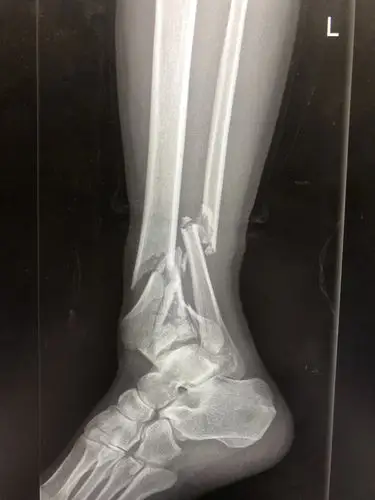

左胫腓骨远端粉碎性骨折并踝关节半脱位

一例严重的胫腓骨远端粉碎骨折

胫腓骨远端粉碎性骨折求手术方案 [病例帖]